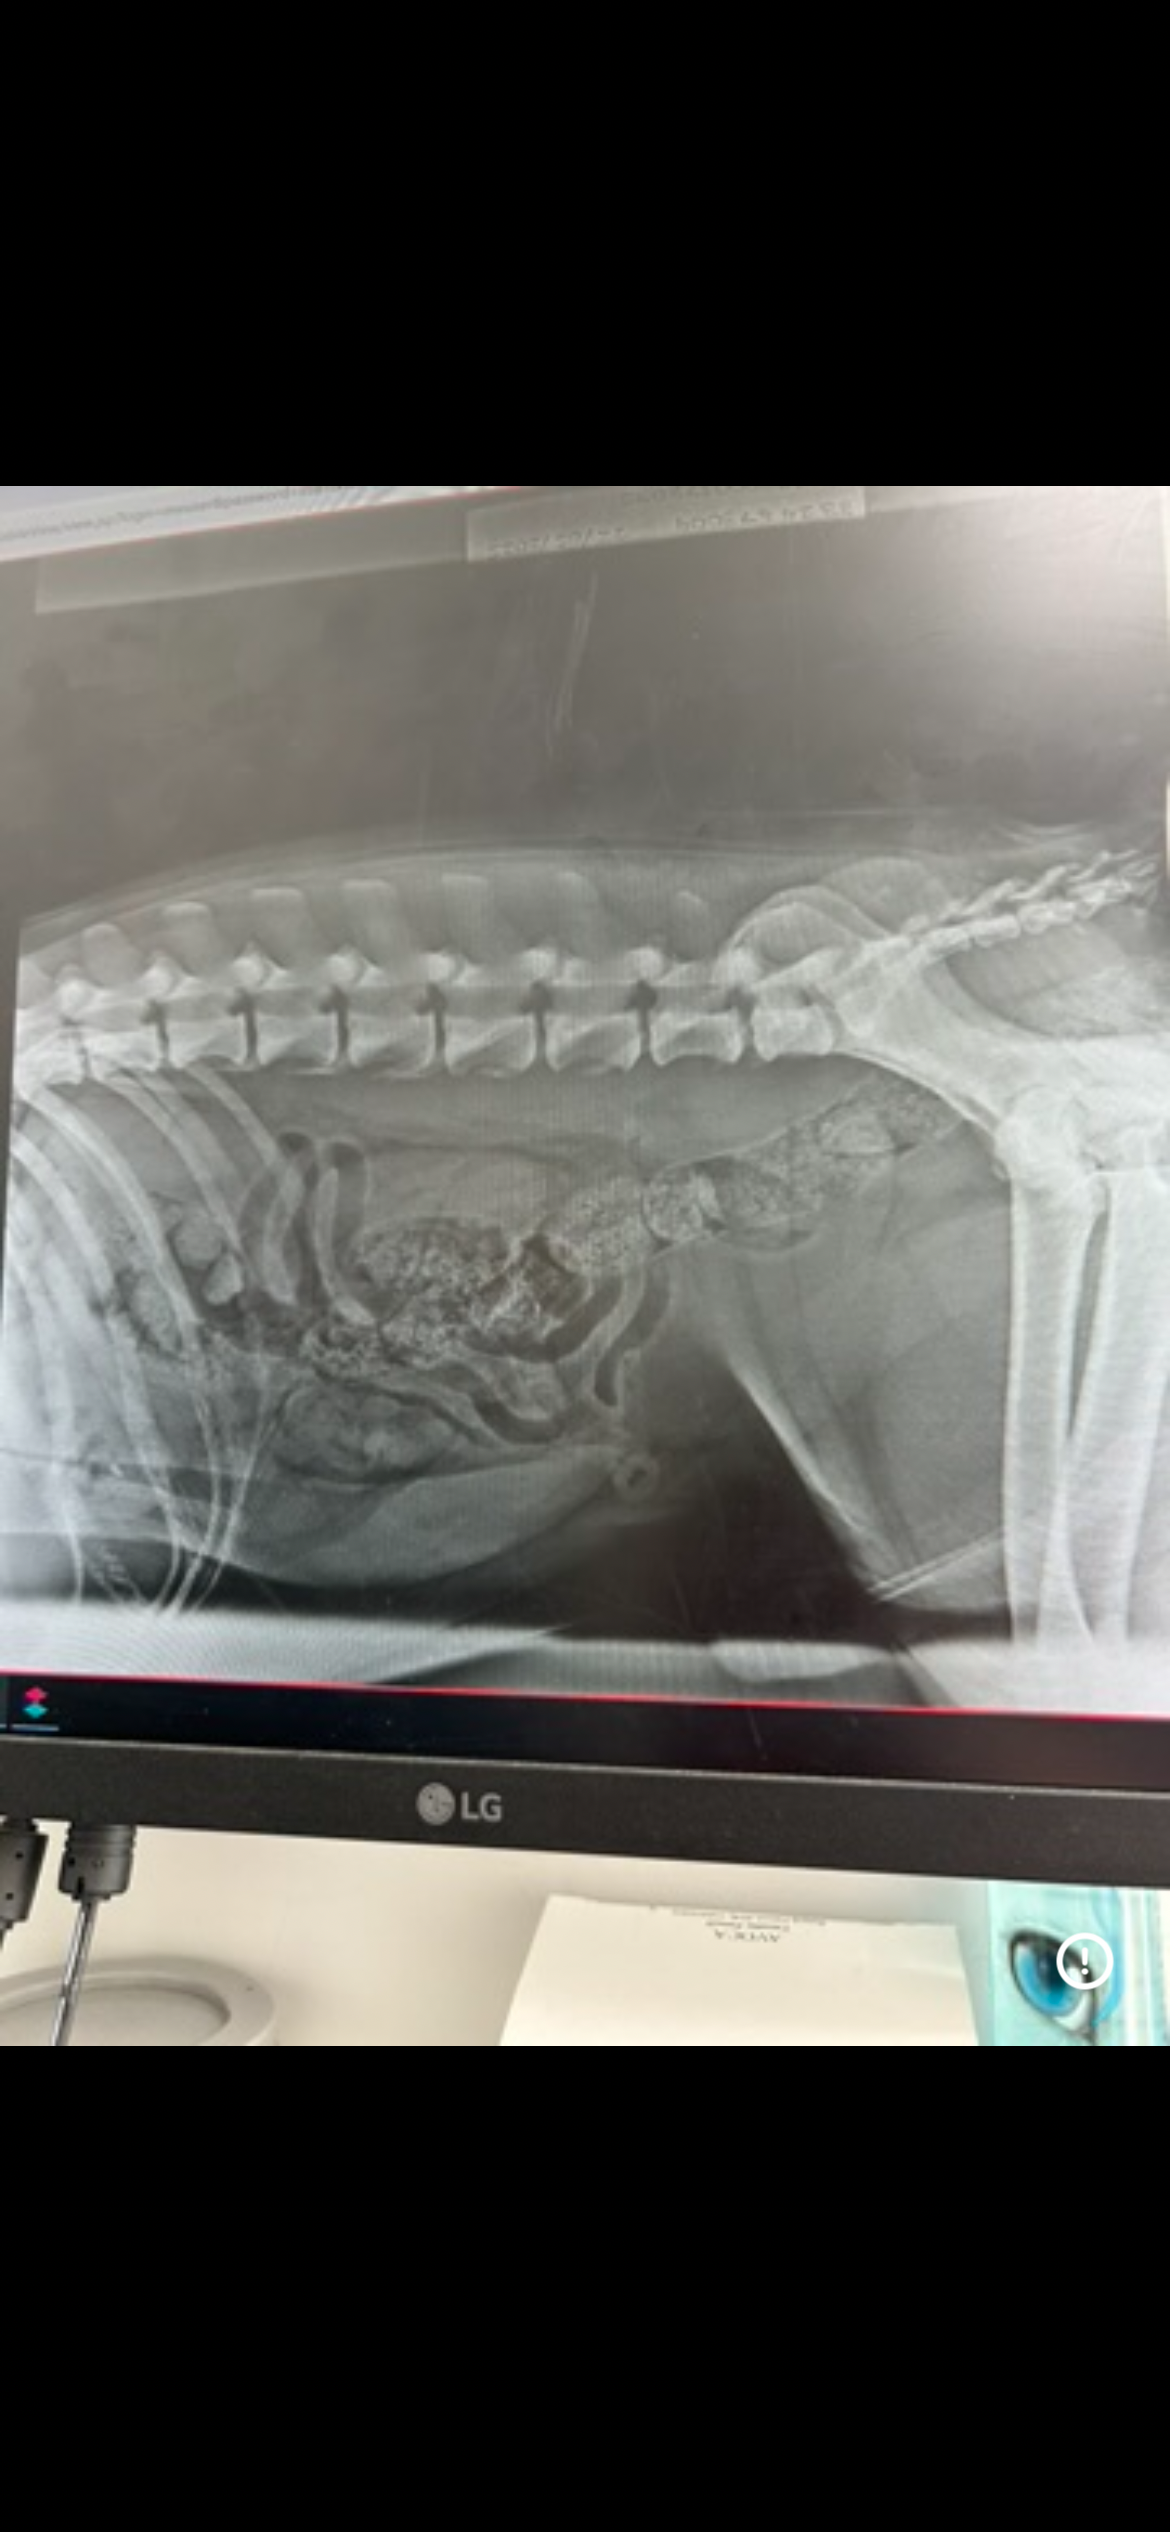

I have hip dysplasia and osteoarthritis, and my x-rays showed that the ligament in my left back leg is torn. The vets said that without TPLO surgery, I will never be able to walk properly again.